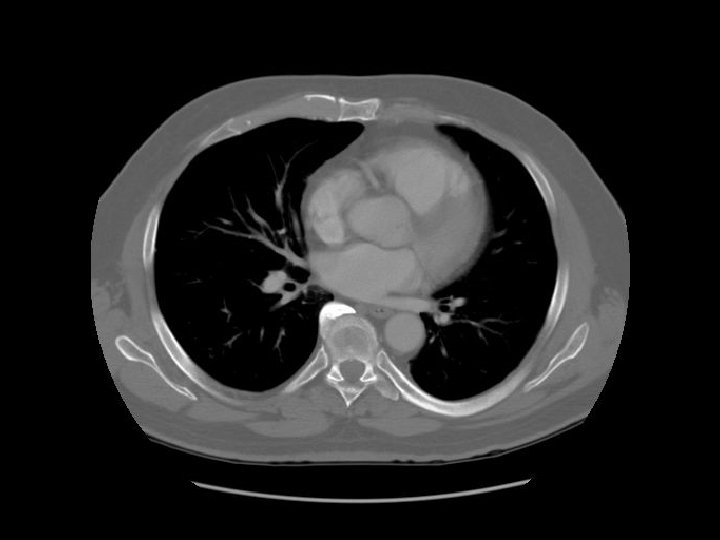

Ascending aorta Main pulmonary artery Descending aorta

Left pulmonary artery Carina

Right pulmonary artery Main pulmonary artery RUL bronchus Left pulmonary artery